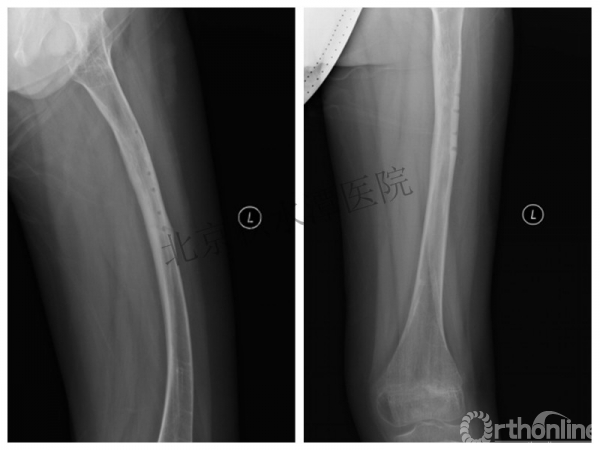

男孩、9岁,滑雪受伤,胫腓骨螺旋形骨折(粉碎性)

这个病例郭教授在积水潭医院骨科高研班时多次讲到,也在互动交流中惊人地看到,了解到现实之令人难以想象!

手法整复,石膏制动!

整复后7天

儿童具备强大的愈合潜力,同样也有极强的塑形能力